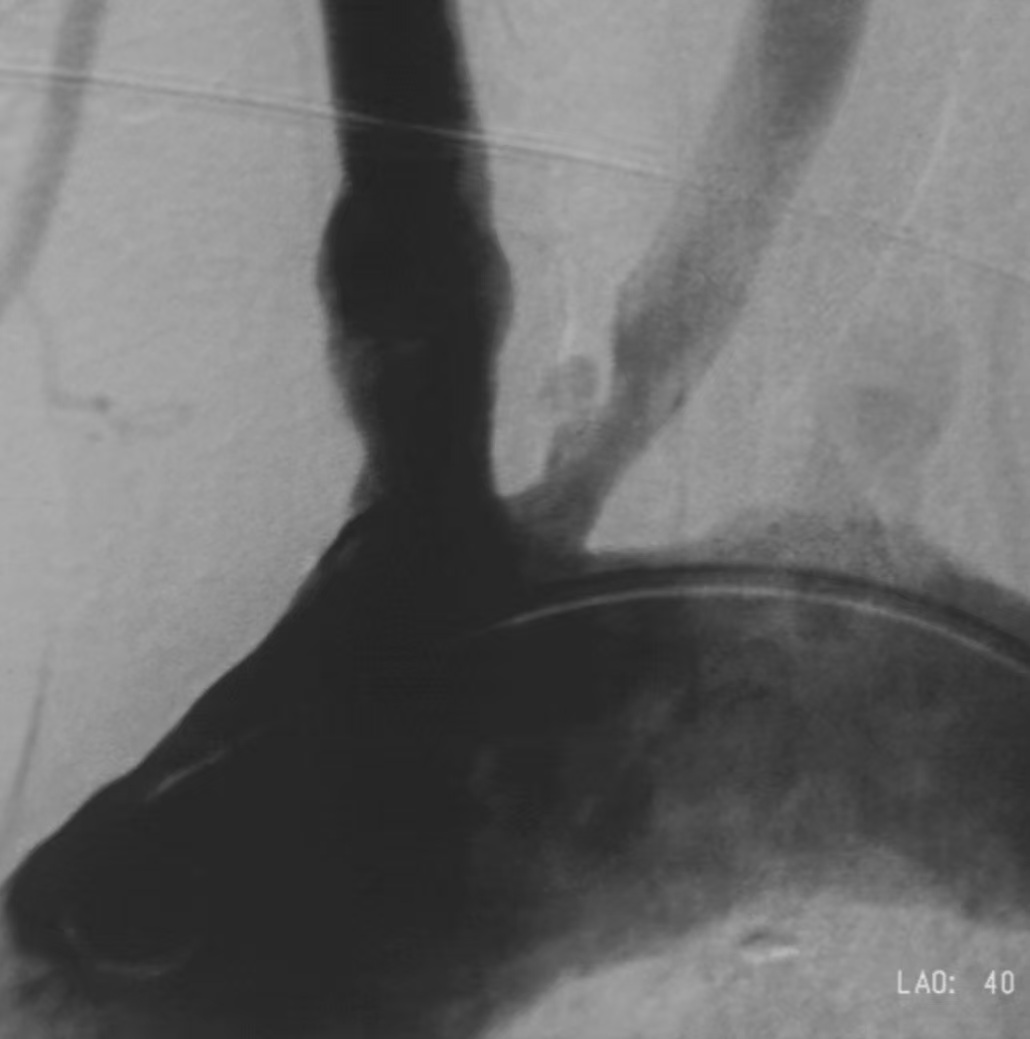

5、血管手术,切除血管内膜和硬化斑或血管扩张支架成形术。